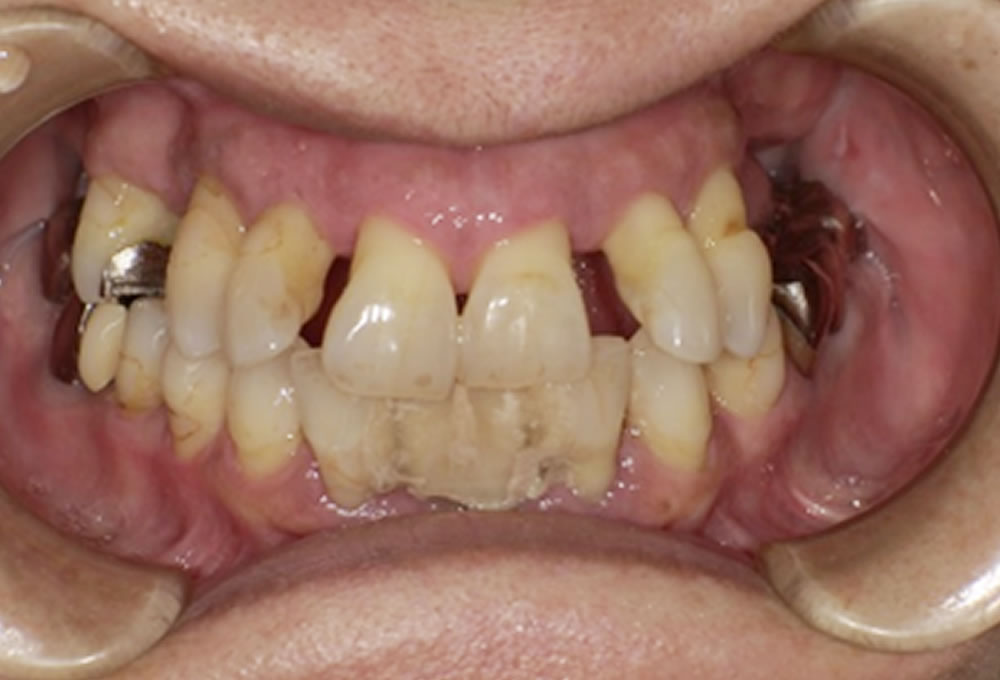

初診時の状態

奥歯から先に悪くなり欠損が進行した結果、噛み合わせのバランスが崩れ、前歯が押し出されて歯並びが乱れている状態でした。

また、1本だけ残っている歯もありましたが、周囲に支えがないため動揺があり、将来的にどこまで長持ちするか懸念される状態でした。